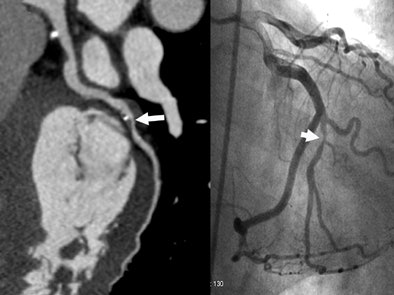

| A 55-year-old man presented with chest pain and history of a 3-year-old right coronary artery (RCA) stent. CTA effective dose using prospectively gated axial (PGA) technique was 0.90 mSv. Volume-rendered image of the coronary tree left depicts the stent (arrow) and many side branches. On the right a curved multiplanar reformatted image of the RCA depicts a widely patent 3.0-mm drug-eluting stent (arrow). |